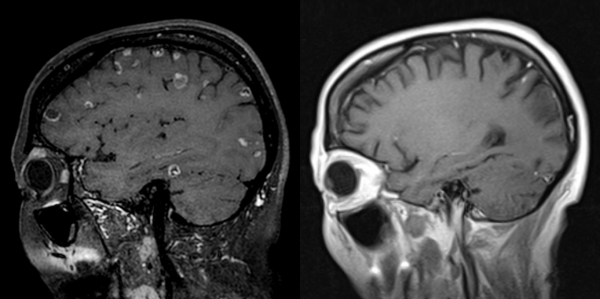

최 교수는 환자의 여러 가지 검사 영상을 확인한 결과 10여 개가 넘는 암 덩어리들이 뇌 속 군데군데를 차지하고 있어, 서울에서 치료를 포기했다는 말을 실감할 수 있었다.

결과는 놀라웠다. 암 세포가 치료에 반응을 보이기 시작하더니 뇌와 폐에 있던 종양들이 약 10개월에 걸쳐 모두 사라졌다.

1개월 시한부 선고를 받은 말기 암 환자가 거의 완치수준의 기적이 일어난 것이다.